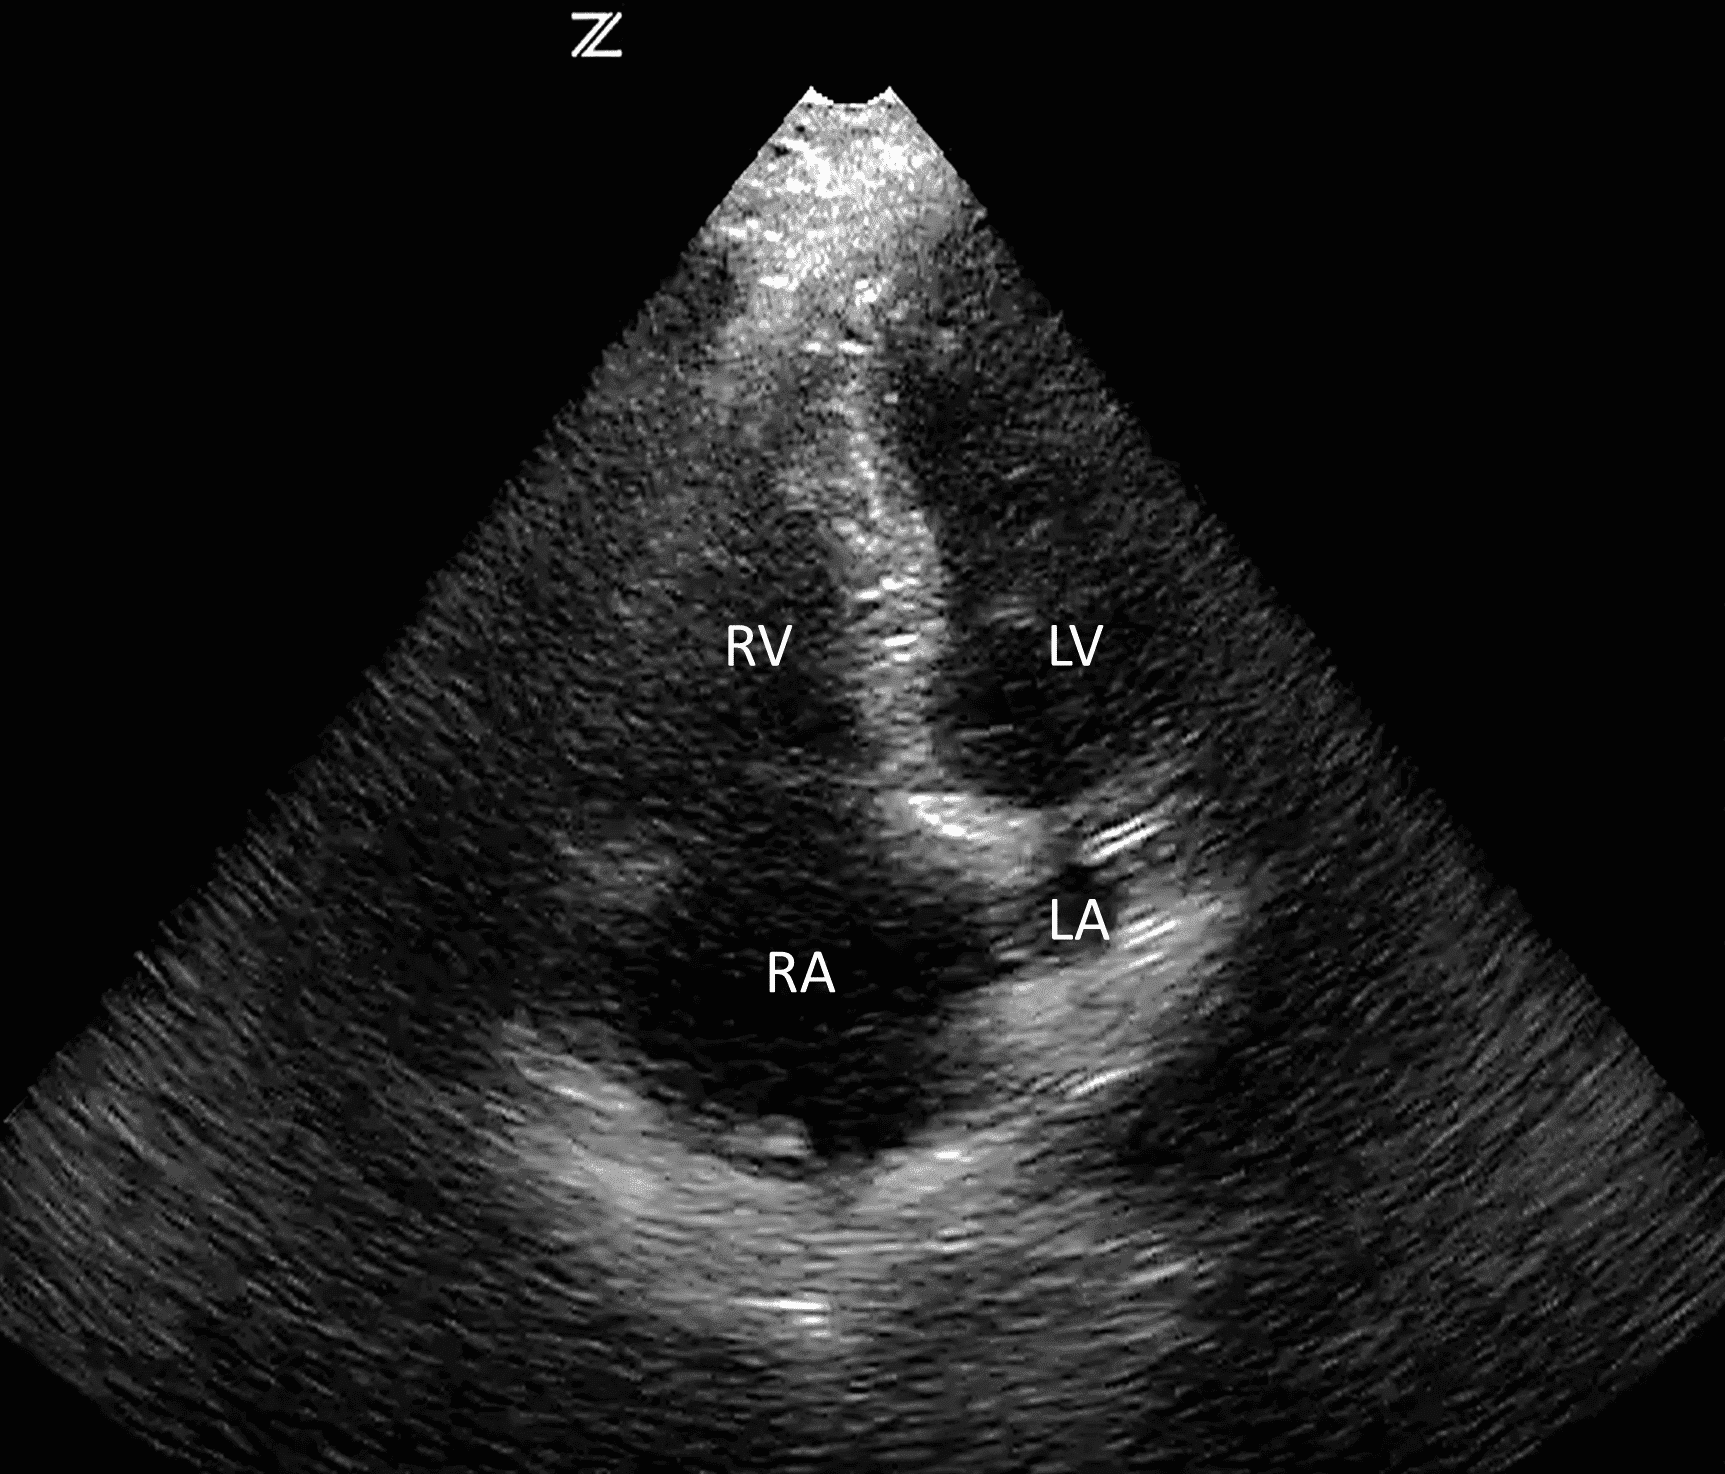

Верхівковий чотирикамерний доступ отримують шляхом розміщення датчика на лівій частині грудної клітки на рівні 4-го або 5-го міжребер’я посередині між середньоключичною та передньою пахвовими лініями, при цьому маркер спрямований праворуч від пацієнта. Може знадобитися розміщення пацієнта в положенні на лівому боці, щоб отримати чотирикамерний вид верхівки (зобр. 4). Цей доступ також дозволяє оцінити колапс правого шлуночка, перикардіальний випіт і серцеву функцію.

Зобр. 4. Нормальний верхівковий чотирикамерний доступ.

RV (правий шлуночок), RA (праве передсердя), LV (лівий шлуночок), LA (ліве передсердя)